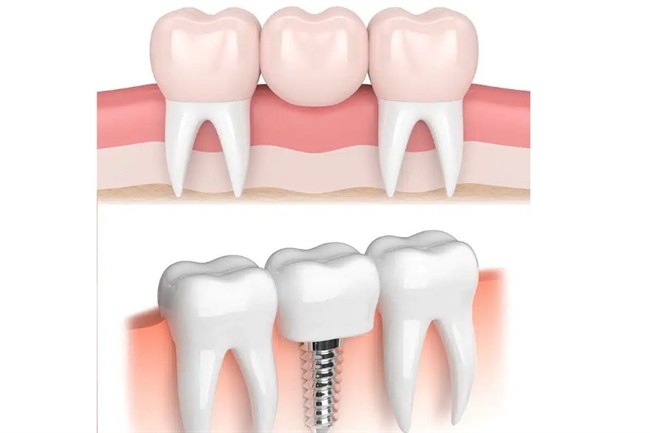

از دست دادن حتی یک دندان، میتواند بهمرور زمان منجر به جابجایی دندانهای مجاور، تحلیل استخوان فک و مشکلات جویدن شود. امروزه دو گزینه اصلی برای جایگزینی دندان از دست رفته بیشتر مورد استفاده قرار میگیرد، پل دندان (بریج) و ایمپلنت دندان. هر کدام مزایا و محدودیتهای خاص خود را دارند و انتخاب نهایی به فاکتورهای متعددی مانند سلامت دندانهای کناری، تراکم استخوان، بودجه و اولویتهای بلندمدت بیمار بستگی دارد.

بریج دندان (پل دندان) یک روش ترمیمی ثابت است که برای جایگزینی یک یا چند دندان از دست رفته استفاده میشود. در این روش، دندانهای مجاور ناحیه بیدندانی به عنوان پایه تراش میخورند و یک پروتز چند واحدی (شامل دندانهای پایه و دندانهای جایگزین) روی آنها سیمان میشود. بریج میتواند از جنس سرامیک، زیرکونیا یا ترکیب فلز و سرامیک ساخته شود.

ایمپلنت دندان یک روش جایگزینی دائمی برای دندانهای از دست رفته است که در آن، یک پایه فلزی (معمولاً از جنس تیتانیوم) داخل استخوان فک قرار میگیرد و پس از جوش خوردن با استخوان، نقش ریشه دندان را ایفا میکند. پس از تکمیل فرایند جوشخوردگی، یک روکش دندانی روی ایمپلنت نصب میشود که از نظر ظاهر و عملکرد، بسیار شبیه دندان طبیعی است. به همین دلیل بسیاری از متخصصان، ایمپلنت را نزدیکترین روش به دندان طبیعی میدانند.

اجزای اصلی ایمپلنت دندان

- فیکسچر (پایه ایمپلنت): بخشی که داخل استخوان فک قرار میگیرد.

- اباتمنت: قطعه رابط بین فیکسچر و روکش.

- روکش ایمپلنت: بخش قابل مشاهده که ظاهر دندان را بازسازی میکند.